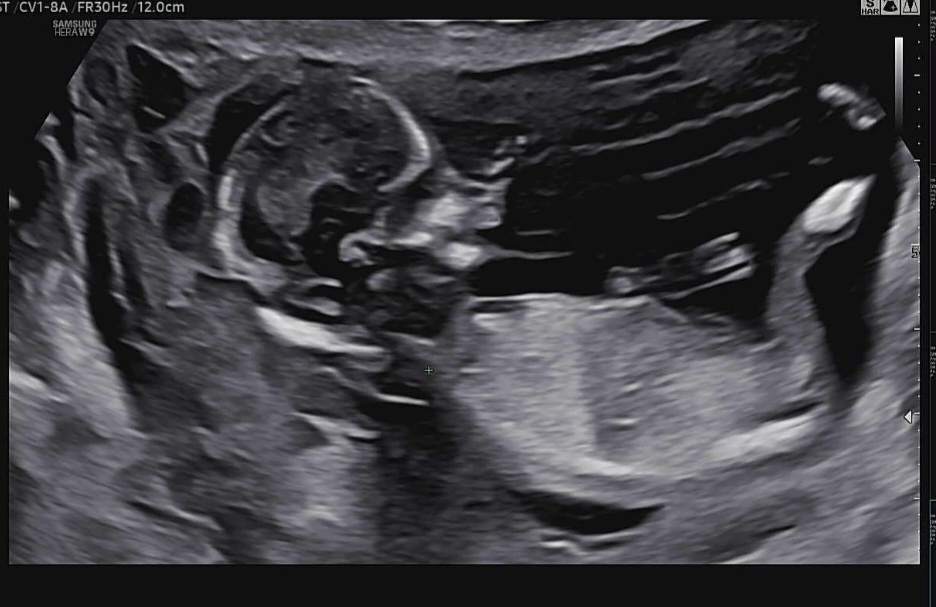

각도법 궁금해요!

딸일까요 아들일까요??

돌기가 잘 안보이는 사진이예요.